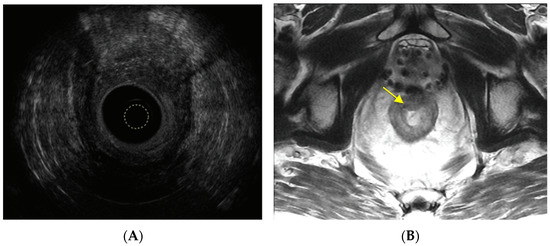

3. Direct Beam Radiation Damages Surrounding Organs

6. Assessment, Surveillance and Diagnosis

- Moreno, C.C.; Sullivan, P.S.; Mittal, P.K. MRI evaluation of rectal cancer: Staging and restaging. Curr. Probl. Diagn. Radiol. 2017, 46, 234–241. [Google Scholar] [CrossRef]